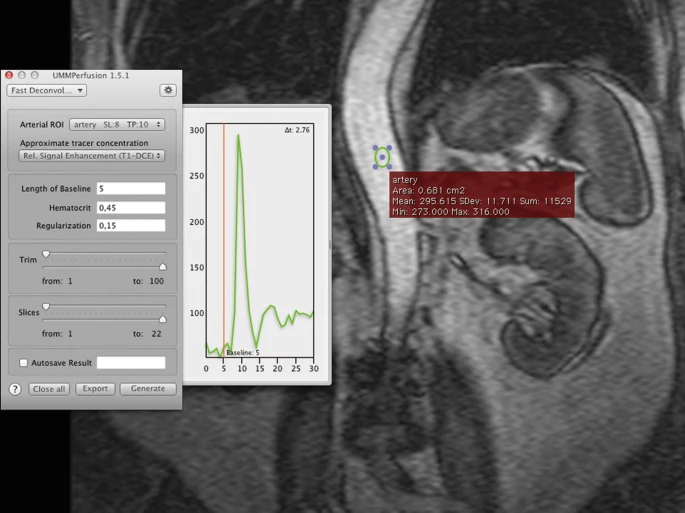

For ensuring correct results all algorithms require an arterial input function (AIF). This function is defined by using the Osirix ROI-tool and by placing/designating a “region of interest” (ROI ) on the abdominal artery. An oval is used as a standard, however all ROI-tools offered by Osirix are supported by UMMPerfusion.

Upon placing a ROI , a chart will appear on the right-hand side of the plugin window, depicting the arterial input function. The aif-color corresponds to the current ROI border color, whereas the vertical line, the base line will always be in red. When a ROI is created, it will be attached to the popup-menu. If several ROIs have been created within this dataset, the desired ROI has to be assigned to its determined position. If only one pixel shall be the source of the AIF, the ROI-Brush- Tool with the size of 1px is to be used in order to specify the smallest ROI possible.

A good ROI selection can be recognized by a large peak on the chart to the right of the plugin-window.

Drag the baseline to a desired position or simply enter the value in the respective text field.

The length of baseline represents the number of images during a certain period of time that are used for signal normalization. For attaining correct results, the baseline should be chosen in a way that the tracer is not yet visible at that point of time. The easiest way to set the baseline is to drag the baseline with the mouse to its desired timeframe in the AIF-chart. The value can alternatively be inserted into the baseline textfield.

Before hitting the generate-button, there is the opportunity to activate the autosave-checkbox to automatically save the results and to generate a report.